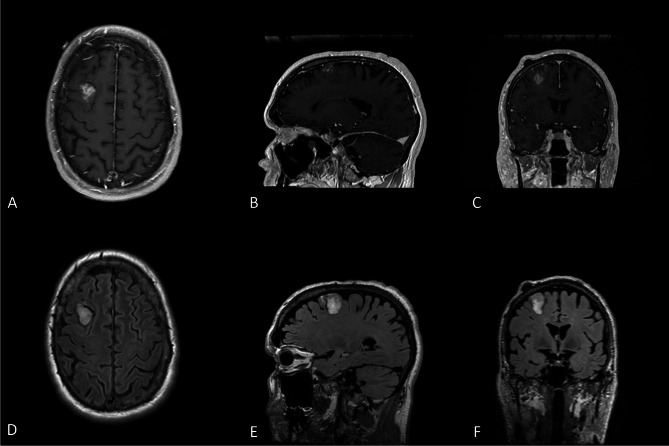

Results: Three patients were identified: two females and one male with a mean age of 49.7 years (range 25-62). No patients had a prior cancer history. One patient had an incidentally discovered tumor, while the other two patients underwent imaging for symptoms of headache, vision changes and extremity weakness. Mean tumor size was 4.0 cm (range 2.8-6) with a wide variation in imaging characteristics. All patients underwent surgical resection and radiographic gross total resection was achieved in all cases. All patients underwent radiation therapy without concurrent chemotherapy. After a median 20 months follow up (range 4.5 to 108.9), two patients experienced tumor progression at 2.7 months and 86.5 months respectively. All patients were alive at last follow up.